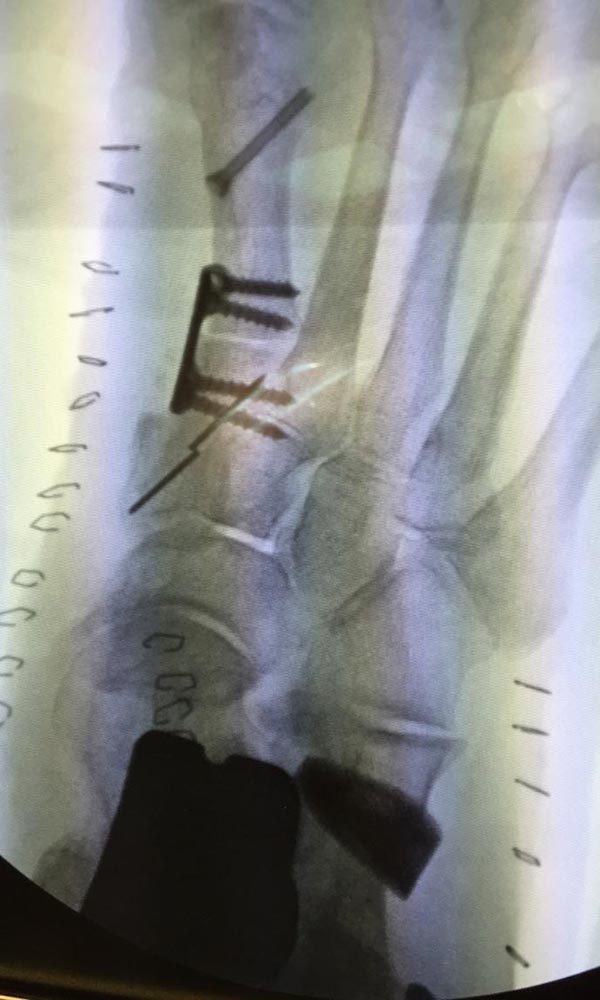

"Surgical misadventure" by another surgeon about 8 years ago. The wrong fixation was used for a flatfoot repair, & the deformity was not corrected. Patient came in with severe foot & ankle pain, with no arch at all. She was unable to play with her grandchild because the pain was so bad, & because she felt unsteady. The old hardware was removed, a lateral calcaneal lengthening osteotomy was performed along with a medial column/1st ray realignment. The ankle was painfully arthritic, & patient elected a total ankle replacement vs. an ankle fusion. She is now able to walk pain free & play with her grandchildren!